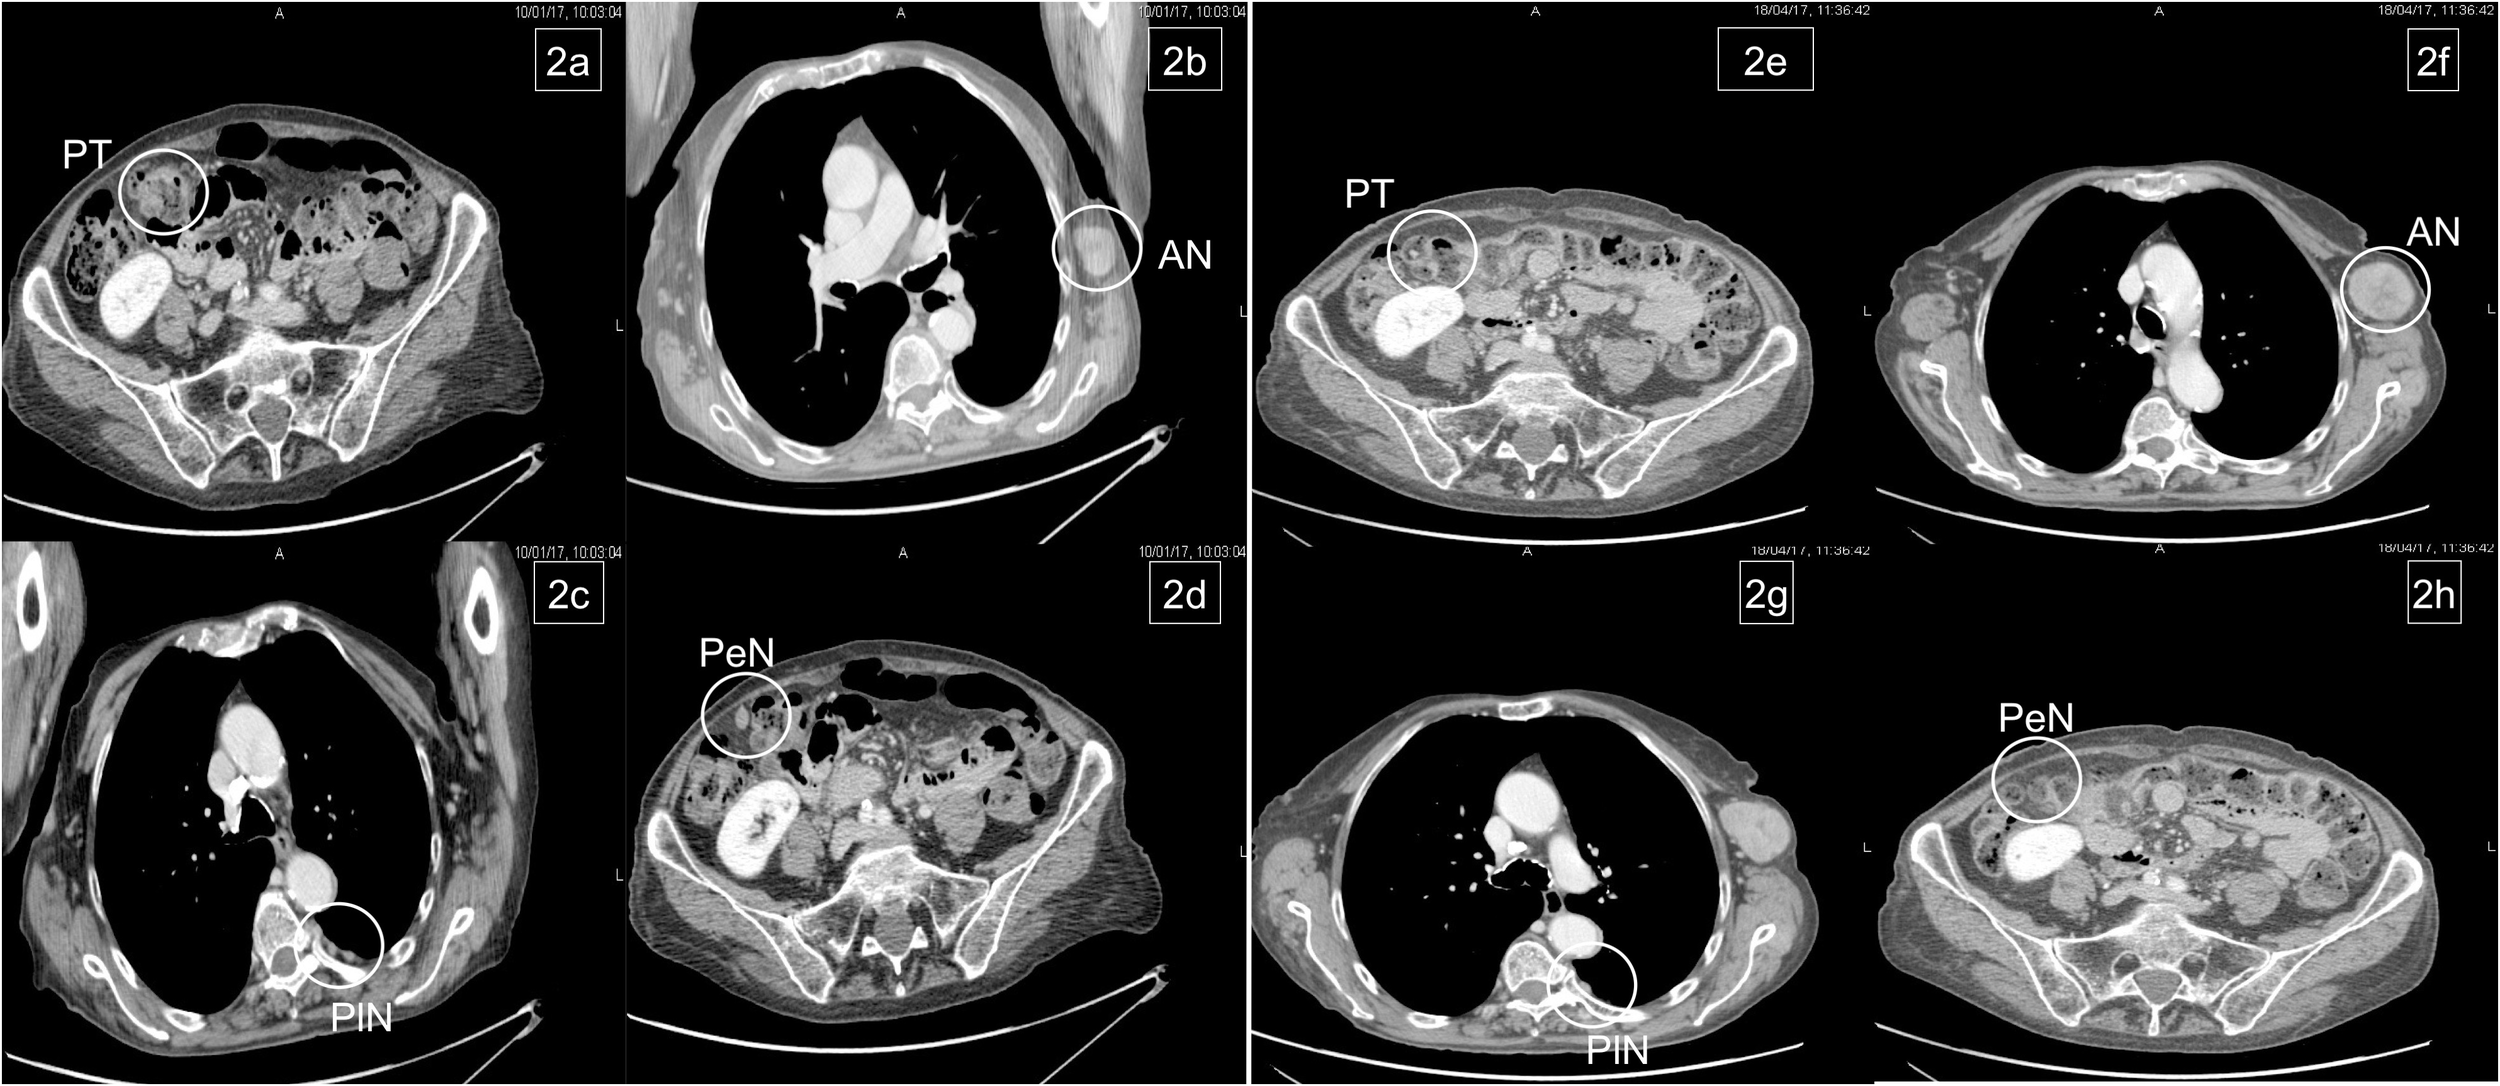

On June 2018, CT scan showed lung progression for evidence of two new lesions (Figures 3A, B). Therefore, the patient resumed 5-FU/FA + panitumumab until March 2019. During this period, disease stability and response on the new lung metastases were achieved (Figures 3C, D) and treatment was stopped temporarily for ocular toxicity (Grade 2, CTCAE 4.0) that was particularly bothersome for the patient.

Figure 3 Pulmonary relapse (A, B). Complete response of lung metastases after reintroduction of chemotherapy (C, D).